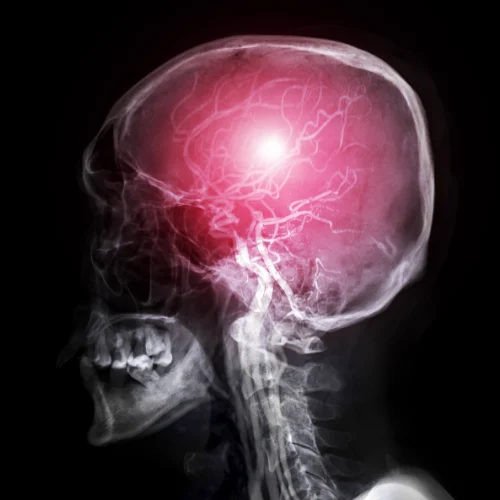

Peripheral Nerve Tumors

Homepage Peripheral Nerve Tumors